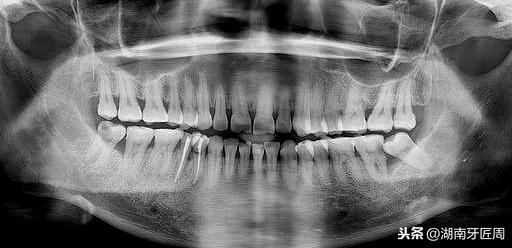

左侧智齿倾斜阻生,顶坏前牙

图片2.右侧智齿倾斜阻生顶坏前牙